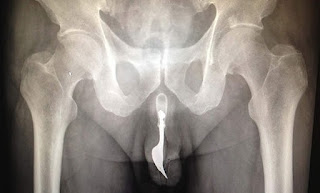

Acudir al doctor, bien sea al médico de cabecera o al servicio de urgencias, es necesario. La infección de orina deberá ser tratada con antibióticos, cuya ingesta y horario de tomas debe ser indicado y controlado por un especialista. El doctor, además, valorará el nivel de infección y tendrá por oportuno hacernos análisis o radiografías que permitan saber o desechar si algún órgano se encuentra considerablemente afectado. También se controlará, tras finalizar el tratamiento, si la infección ha remitido por completo. No debe preocuparnos el pensar que el profesional nos interrogará acerca del posible origen del brote infeccioso. Por el contrario, sus intenciones no alcanzan a saber el motivo de la infección, que puede ser múltiple, sino saber cómo combatirla y lograr finiquitarla.

Otra consecuencia médica con la que podríamos enfrentarnos causada por una sesión de sounding, o más bien por una serie continuada de ellas, que apareciera no inmediatamente sino a largo plazo, sería la estenosis uretral. Esta disfunción haría referencia a una estrechez causada en cualquiera de los tramos de la uretra previa a la curvatura infrapúbica, pudiendo darse así tanto en la denominada uretra peneana (porción de uretra que atraviesa el pene externo), como ya dentro del tronco en la uretra bulbar (tramo de uretra localizado en la zona bulbar del pene interno, bajo la próstata). La aparición de estenosis no es habitual, pudiendo ser consecuencia de diversos motivos, encontrando entre ellos, y en relación con el sounding, una laceración en las paredes uretrales que conllevase tal cicatrización que ésta alcanzase a estrechar el conducto urinario, provocando a raíz de tal compresión en el caño diversos problemas a la hora de orinar.

Una práctica inadecuada de sounding que conllevase raspado, lesiones o traumatismo en el interior de la uretra, podría derivar en una posterior estenosis uretral. Aunque tal arañazo pudiera aparecer en cualquier tramo de la uretra anterior a la curvatura infrapúbica, sería la uretra bulbar la más propensa a padecer sobre ella estenosis uretral bulbar, ya que es este tramo el que, a la hora de introducir un objeto rígido, parase la metida del útil ante la presencia de la curvatura infrapúbica, siendo las paredes uretrales de este tramo las que recibieran el impacto del objeto contra ellas, pudiendo ser desafortunadamente raspadas.

Si la estenosis no es muy grave, una serie de dilataciones uretrales prescritas y controladas por el doctor podrían terminar con el estrechamiento provocado por la cicatrización en el interior de la uretra. Sin embargo, si la estenosis es seria, sólo quedaría la intervención quirúrgica médica.